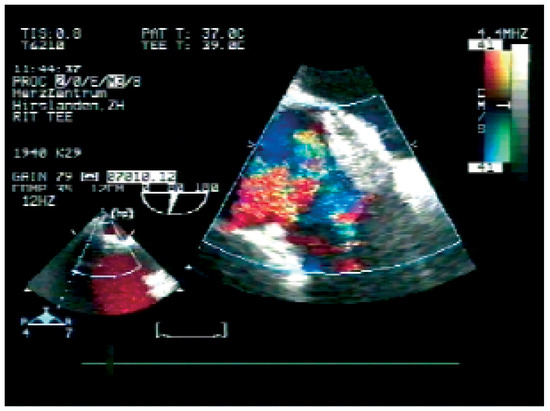

Coronary and Peripheral Thromboembolism from a Giant Left Atrium

by Marcello Di Valentino, Andrea Menafoglio, Ludwig von Segesser, Jeanne-Marie Segatto and Augusto Gallino

Cardiovasc. Med. 2006, 9(1), 28; https://doi.org/10.4414/cvm.2006.01144 - 27 Jan 2006

Abstract

We report the case of a patient with a history of mitral valve replacement and a giant left atrium with acute transmural anterior myocardial infarction and concomitant acute occlusion of the right superficial femoral artery [...] Full article